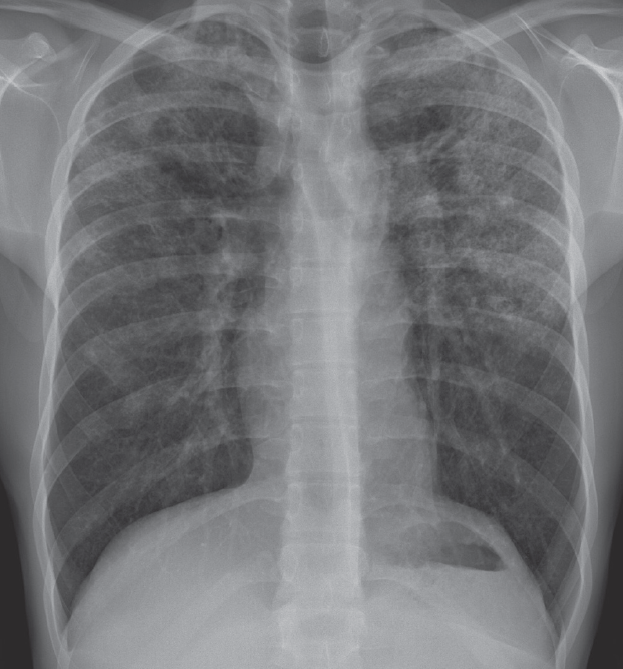

Lung cancer

05/13/2014

Alvin Wycoco, MD; Shebene Chacko, MD; Rafael Ilyayev, MD; Rajat Mukherji, MD

A 92-year-old female with a history of hypertension, diabetes mellitus, and breast cancer presented with a fever of 2 days duration and a cough productive of whitish sputum.